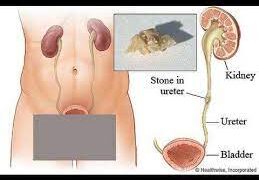

Read moreডা. মো. অলিউল ইসলাম মারুফ মানবদেহে কয়েকটি স্থানে পাথর হয়। যেমন—কিডনি, মূত্রনালি, পিত্তথলি (পিত্তনালি ও লিভারের ভেতরে), অগ্ন্যাশয়, প্রোস্টেট ইত্যাদি।...

Read moreডা: তারেক আনোয়ার কিডনির পাথর এখন অনেকের মধ্যেই দেখা যায়। এটা একটা কিংবা উভয় কিডনিতেই হতে পারে। এটা সাধারণত ৩০-৬০...